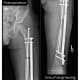

As instrumentation and techniques evolve, Honcharuk has more options for her patients. Instead of traditional extramedullary nails for limb-lengthening, for example, she may use intramedullary nails. She also employs a technique to place the intramedullary nails next to the bone in patients whose bones are too narrow to allow insertion of a nail into the canal. She describes the technique as a “workaround” for her smallest patients to avoid using an external frame while still providing timely treatment. She also notes that a new nail is expected to reach the market in the next year that will allow patients to bear full weight on the treated limb.